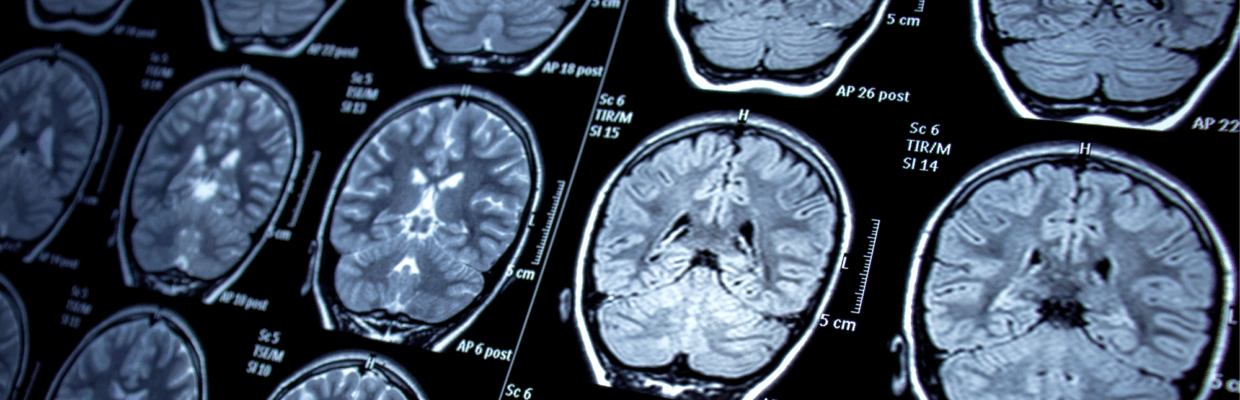

A new study launching today will use revolutionary long term seizure tracking technology to monitor and potentially predict patterns in epileptic seizures using continuous, reliable, and objective data collection of brain activity in people with drug-resistant epilepsy.

Subcutaneous (under the skin) implanted electroencephalogram (EEG) is a new technology. Conventional EEG technology either requires the person to be admitted to hospital or be tested at home, using EEG electrodes glued to their scalp, which can be undertaken for only a few days. NHS waiting lists for these tests can vary from months

to years.

Subcutaneous implanted EEG, the technology being trialled in this study, enables researchers to continuously record EEG in an unobtrusive way, for up to 15 months, while the person lives their life completely normally.

The trial will recruit 33 people with drug resistant epilepsy and implant a miniaturised electroencephalogram (EEG) device just under their scalp during a minimally invasive, twenty minute procedure that is performed under local anaesthetic. Researchers will then monitor each person’s brainwaves over six months. By tracking the brainwaves, researchers can accurately count the person’s seizures, which enables them.